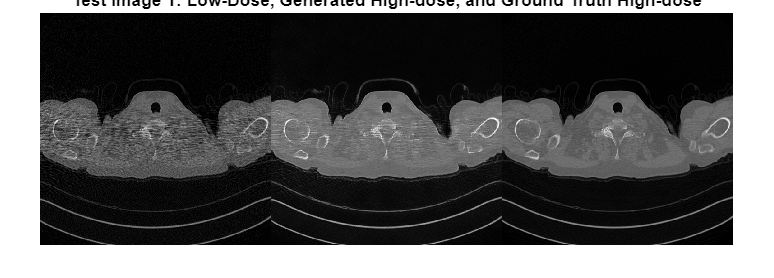

Display the input low-dose CT, the generated high-dose version, and the ground truth high-dose image in a montage. Although the network is trained on data from a single patient scan, the network generalizes well to test images from other patient scans.

imshow([imLowDoseTest,imHighDoseGenerated,imHighDoseGroundTruth]) title("Test Image "+num2str(idxToTest)+ ... ": Low-Dose, Generated High-dose, and Ground Truth High-dose")